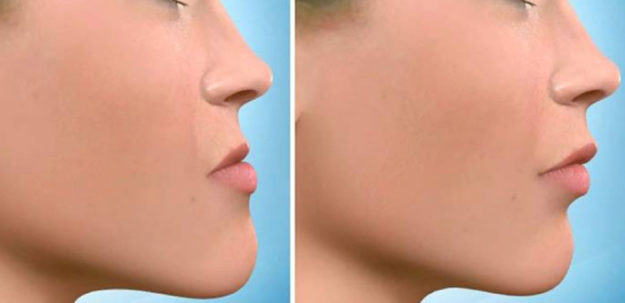

Botox: Arma Contra o Bruxismo

O cirurgião-dentista Ronaldo Rettore Junior: “a aplicação do botox não garante a cura e, sim, apenas o controle do quadro, que pode ocasionar desgaste e quebra dos dentes.” O ranger de dentes, o chamado bruxismo, principalmente durante o sono, é frequente em adultos e crianças e tem graves consequências. Além do desgaste e amolecimento dos… Continue lendo…